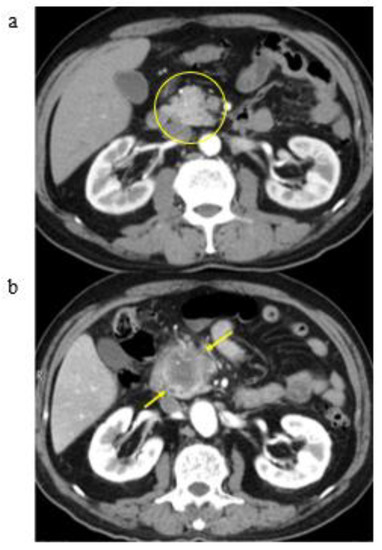

3.2. A Representative Case and Classification by Specific Abnormality of the Pancreas

| Group A | K-sign | 15 (36.6) | 5 (33.3) | 7 (46.7) | 1 (6.7) | 2 (13.3) |

| K-sign + pancreatic duct patency | 9 (21.9) | 4 (44.4) | 5 (55.6) | 0 (0) | 0 (0) | |

| Group B | Localized fatty change | 7 (17.0) | 4 (57.1) | 0 (0) | 3 (42.9) | 0 (0) |

| Localized fatty change + pancreatic duct patency | 1 (2.4) | 0 (0) | 0 (0) | 1 (100) | 0 (0) | |

| Group C | No abnormality | 9 (21.9) | 4 (44.4) | 3 (33.3) | 1 (11.1) | 1 (11.1) |